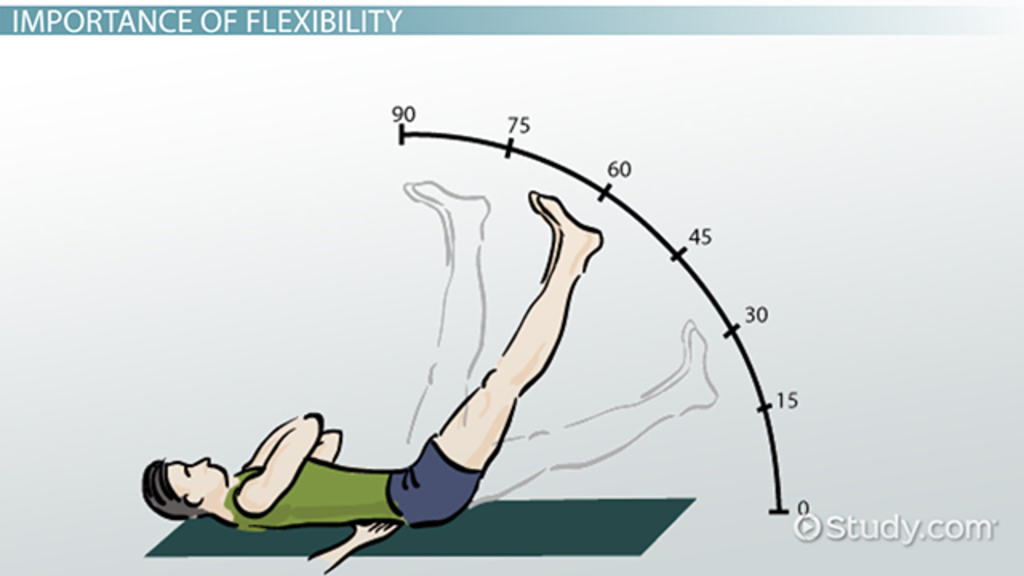

Range of motion is the capability of a joint to go through its complete degree

Active range of motion is the range of motion that can be achieved by voluntary movement from contraction of the associated skeletal muscles. For example, the active range of motion to allow the elbow to bend requires the biceps to contract while the triceps muscle relaxes.